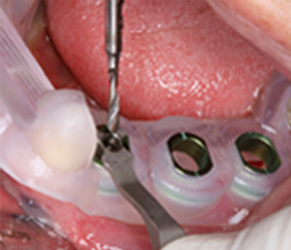

가이드 수술

분석한 정보로 보조장치와 보철물을 정밀하게 제작하여 임플란트 수술에 적용합니다.

수술계획

3차원 컴퓨터 입체 영상을 통해 치조골의 구조와 신경위치를 분석하여 임플란트의 식립위치, 방향 등을 결정합니다.